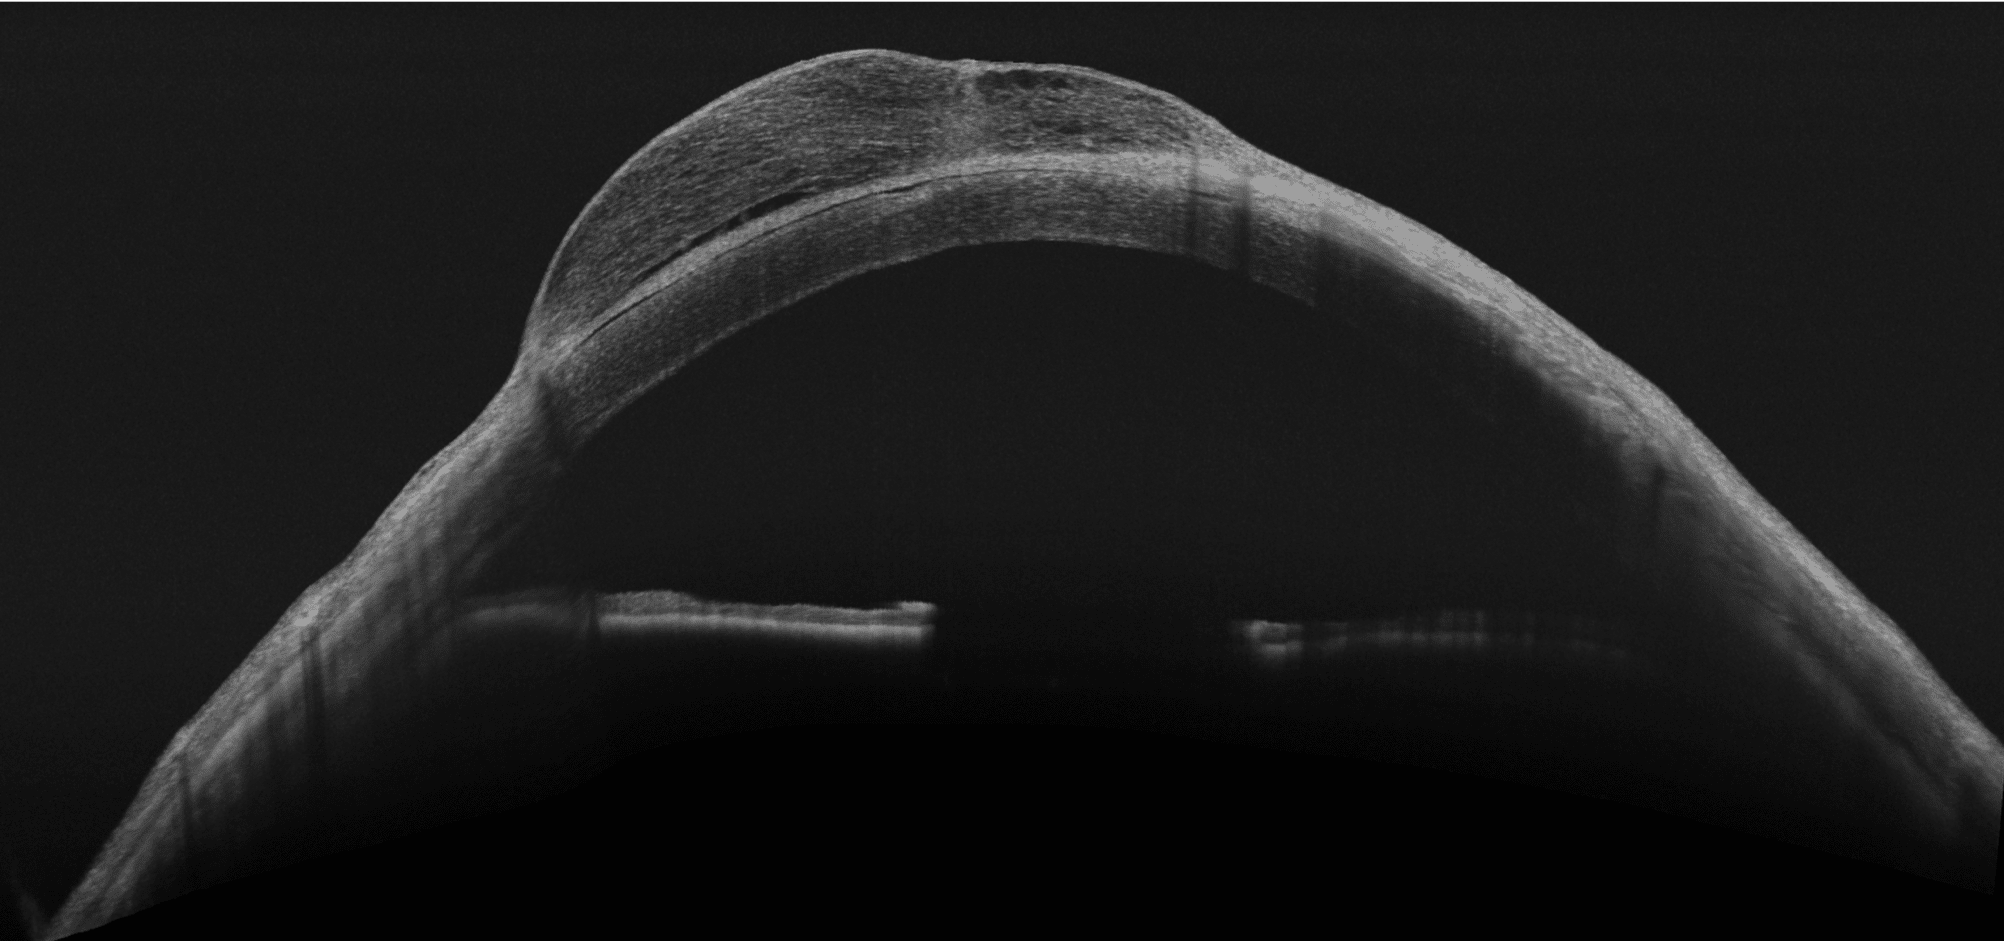

- HD Anterior Scan with Anterior OCTA